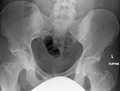

The radiographic appearance of osteopoikilosis on an x-ray is characterized by a pattern of numerous white densities of similar size spread throughout all the bones. This is a systemic condition. It must be differentiated from blastic metastasis, which can also present radiographically as white densities interspersed throughout bone. Blastic metastasis tends to present with larger and more irregular densities in less of a uniform pattern. Another differentiating factor is age, with blastic metastasis mostly affecting older people, and osteopoikilosis being found in people 20 years of age and younger.

Osteopoikilosis of the hips on CT.